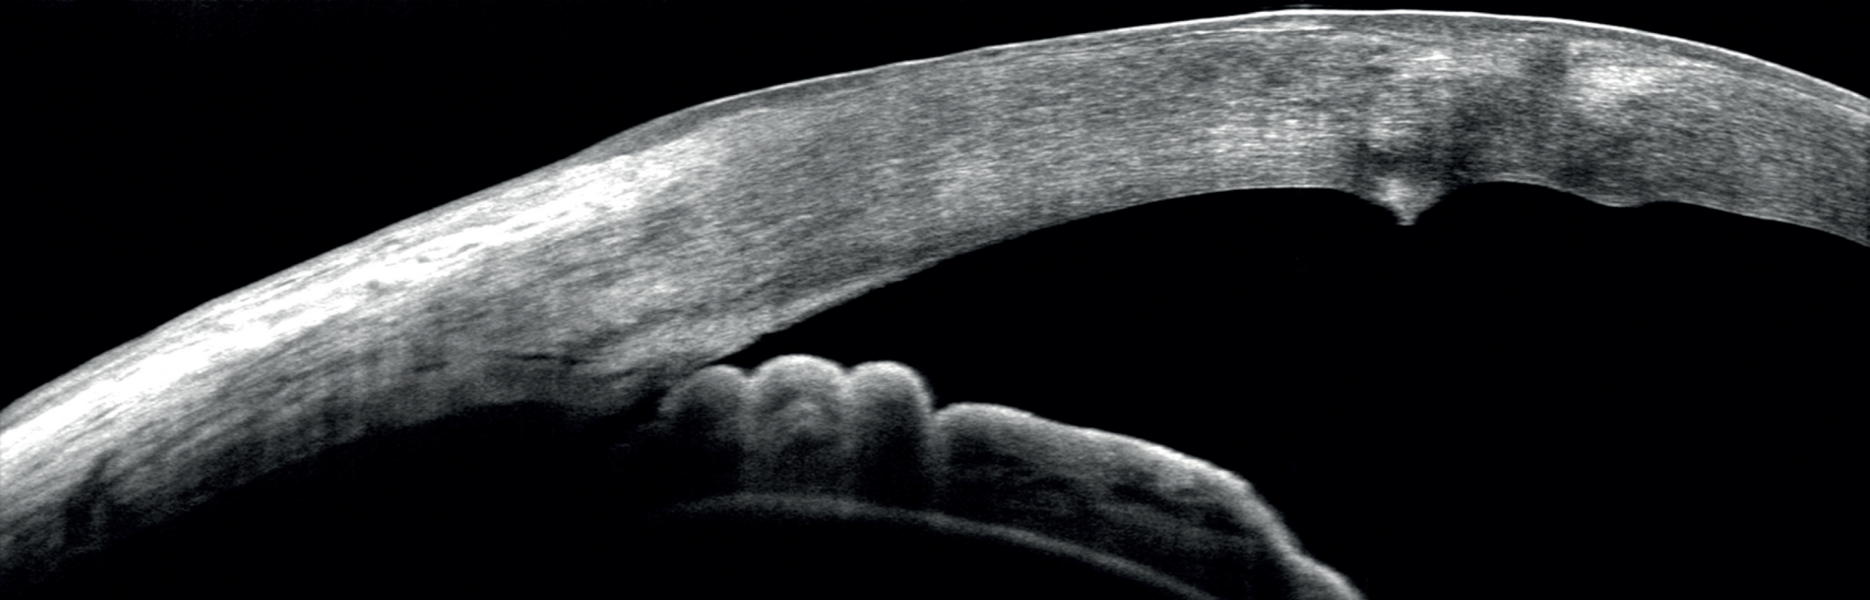

- Παχυμετρικός χάρτης του κερατοειδούς χρήσιμος στην προεγχειρητική εκτίμηση πριν από το Laser μυωπίας και στην πρώιμη διάγνωση παθήσεων όπως ο κερατόκωνος.

- Ποσοτική μέτρηση της γωνίας του προσθίου θαλάμου η οποία γίνεται χωρίς επαφή με τον οφθαλμό και αντικαθιστά τη δυσάρεστη για τον ασθενή εξέταση της γωνιοσκοπίας.

- Εκτίμηση των παθήσεων και των τραυμάτων του κερατοειδούς, του προσθίου θαλάμου και του φακού.